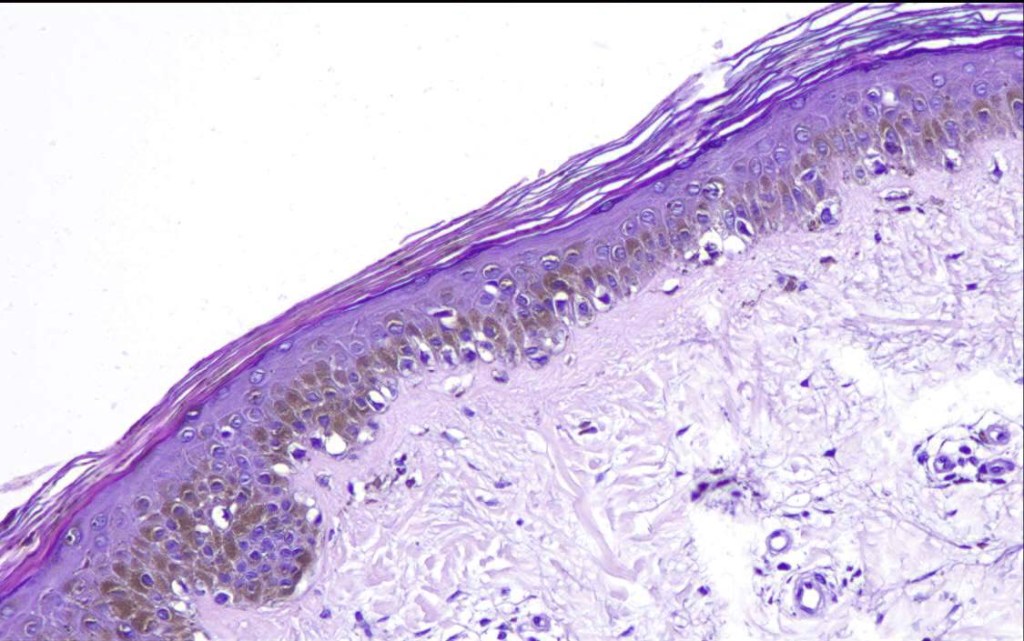

- A broad lentiginous proliferation of atypical melanocytes unasscoiated with any loss of the rete ridges

2. Melanocytes generally small, epithelioid (rather than spindled) with either vesicular nuclei and prominent nucleoli or are hyperchromatic.

5. Grey/greenish cytoplasm (due to fine melanin pigment) occasionally encountered